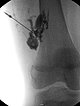

Digital subtraction angiography after direct puncture of the venous malformation during sclerotherapy. In addition to the lesion, direct communicating veins with the deep conducting vein system are visible. These were occluded with viscous alcohol gel by direct puncture.